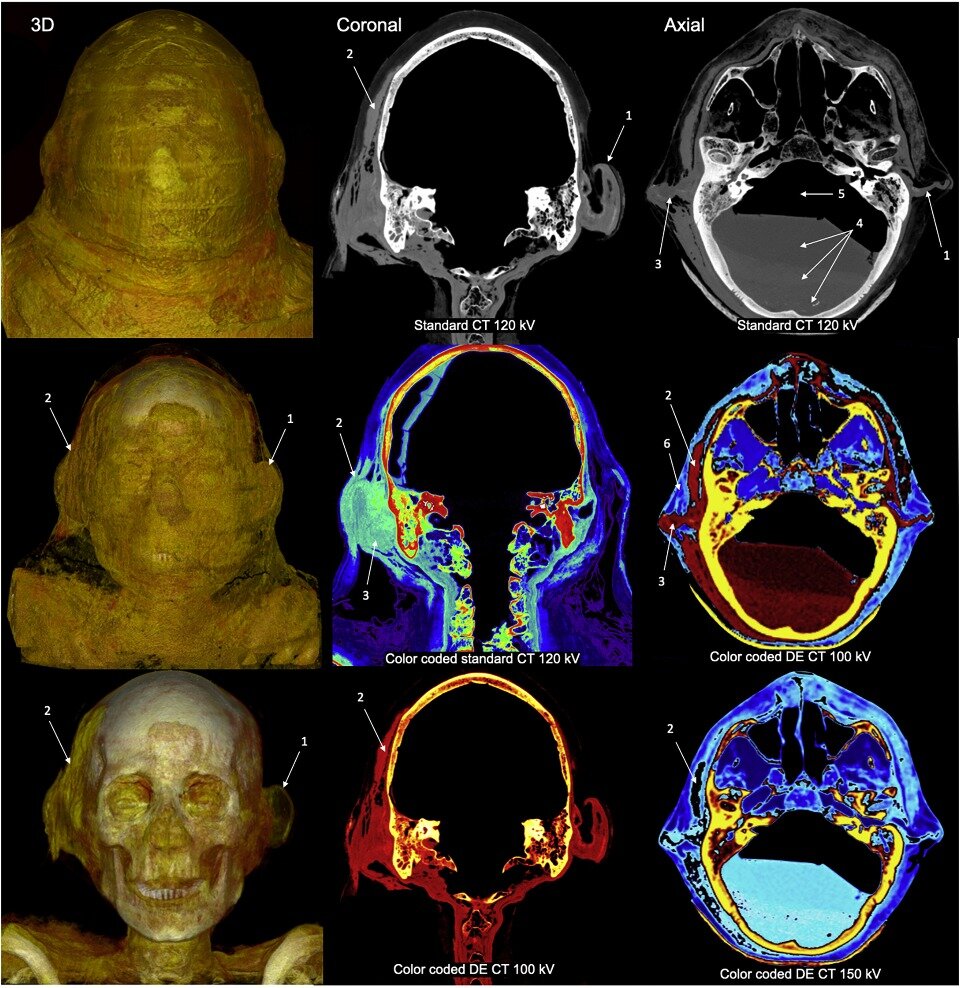

Ученые сделали компьютерную томографию мумии Джед-Хора из немецкого Гейдельберга, которая представляет собой останки взрослого мужчины, жившего в Египте, по всей видимости, в IV–I веках до нашей эры. Исследование его черепа показало, что он пострадал от острого мастоидита, который, вероятно, вызвал смертельные осложнения – например, менингит или абсцесс мозга. Примечательно, что к височной кости этого человека, похоже, приложен некий лечебный компресс, который не убрали во время мумификации. Об этом сообщается в статье, опубликованной в журнале European Annals of Otorhinolaryngology, Head and Neck Diseases. Масштабные раскопки в Египте длятся уже не первое столетие. За это время в распоряжение исследователей попали тысячи хорошо сохранившихся древних тел, многие из которых до сих пор мало изучены. В последние годы на помощь ученым пришли современные методы палеорадиологии, которые позволили существенно продвинуться в изучении биоархеологических материалов. В отличие от традиционных пат

С помощью компьютерной томографии исследователи решили выяснить, какие проблемы со здоровьем были у этого мужчины. Ученые обнаружили, что полость сосцевидного отростка правой височной кости, барабанная полость, наружный слуховой проход и некоторые другие места заполнены серым веществом, которое, похоже, представляет собой засохший гной. Кроме того, на внешней стороне правой височной кости этого человека лежит некий компресс размером примерно 7×10×0,7 сантиметра, который заметно отличается по плотности от окружающих льняных бинтов, покрывающих мумию.

По мнению исследователей, мумифицированный Джед-Хор, по всей видимости, пострадал от острого мастоидита. Они предполагают, что это воспалительное заболевание привело к развитию тяжелых внутричерепных осложнений (например, менингита или абсцесса мозга), от чего в конечном счете мужчина и скончался. При этом обнаруженный компресс, по словам авторов работы, мог представлять собой средство лечения – возможно, он был пропитан неким лечебным снадобьем (от масла или меда до экскрементов кошки или крокодила). Однако в таком случае остается непонятно, почему этот компресс не убрали во время мумификации.